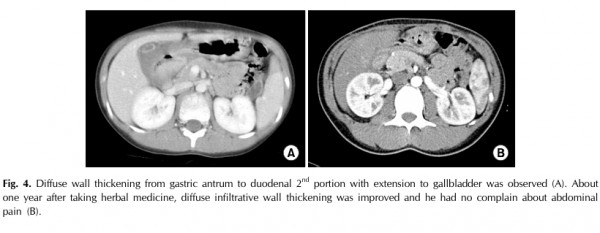

두 번째 증례는 94년생 남아로

위에서 소장까지 광범위하게 염증근섬유모세포종양이 침범하여 수술 불가능 판정을 받은 후,

한약 투약을 시작하였고 투약 후 CT 상에서 위벽을 포함한 십이지장, 소장의 두께가 감소하는 소견이 관찰되었고,

복통과 같은 증상 또한 모두 소실된 케이스입니다.

약 1년의 복용 후, 복용을 중단하였지만 임상적 증상이나 CT 소견 상 악화되지 않고 지속적으로 변화 없이 잘 유지되고 있는 증례입니다.